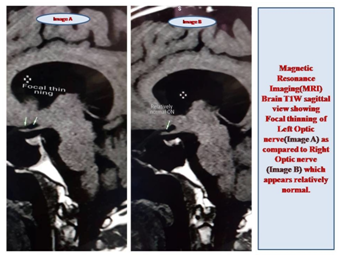

The radiological diagnosis of SOD is best established by Magnetic Resonance Imaging (MRI) of Brain. It identifies the hypoplasia of olfactory bulb, optic nerve and optic chiasma and certain malformations in the brain present congenitally.7 Some of the malformations of the brain are schizencephaly, absent septum pellucidum, abnormal ventricles8 (Figure 1-4).

Figure 4 Image A shows MRI Brain T1W sagittal view showing focal thinning of left optic nerve as compared to the right optic nerve (Image B), which seems to be relatively spared.